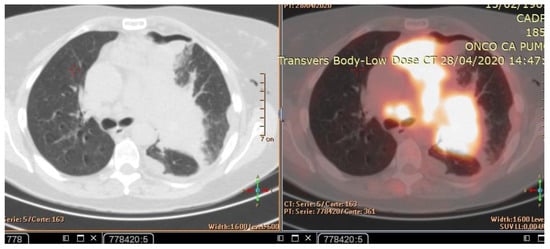

A CT scan and biopsy showed the presence of small cell lung cancer, stage IVA (T4 N3 M1a). The CT scan showed images of a hypermetabolic left pulmonary hilar tumor (Figure 3).

Figure 3. CT scan image showing hypermetabolic left pulmonary hilar tumor from male SCC patient.